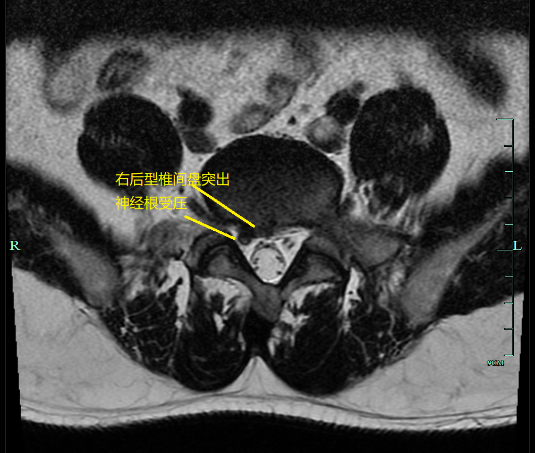

男,25 岁, L5/S1 椎间盘突出,左后型,S1 神经根受压

男,39 岁, L5/S1 椎间盘突出(右后型)及神经根受压